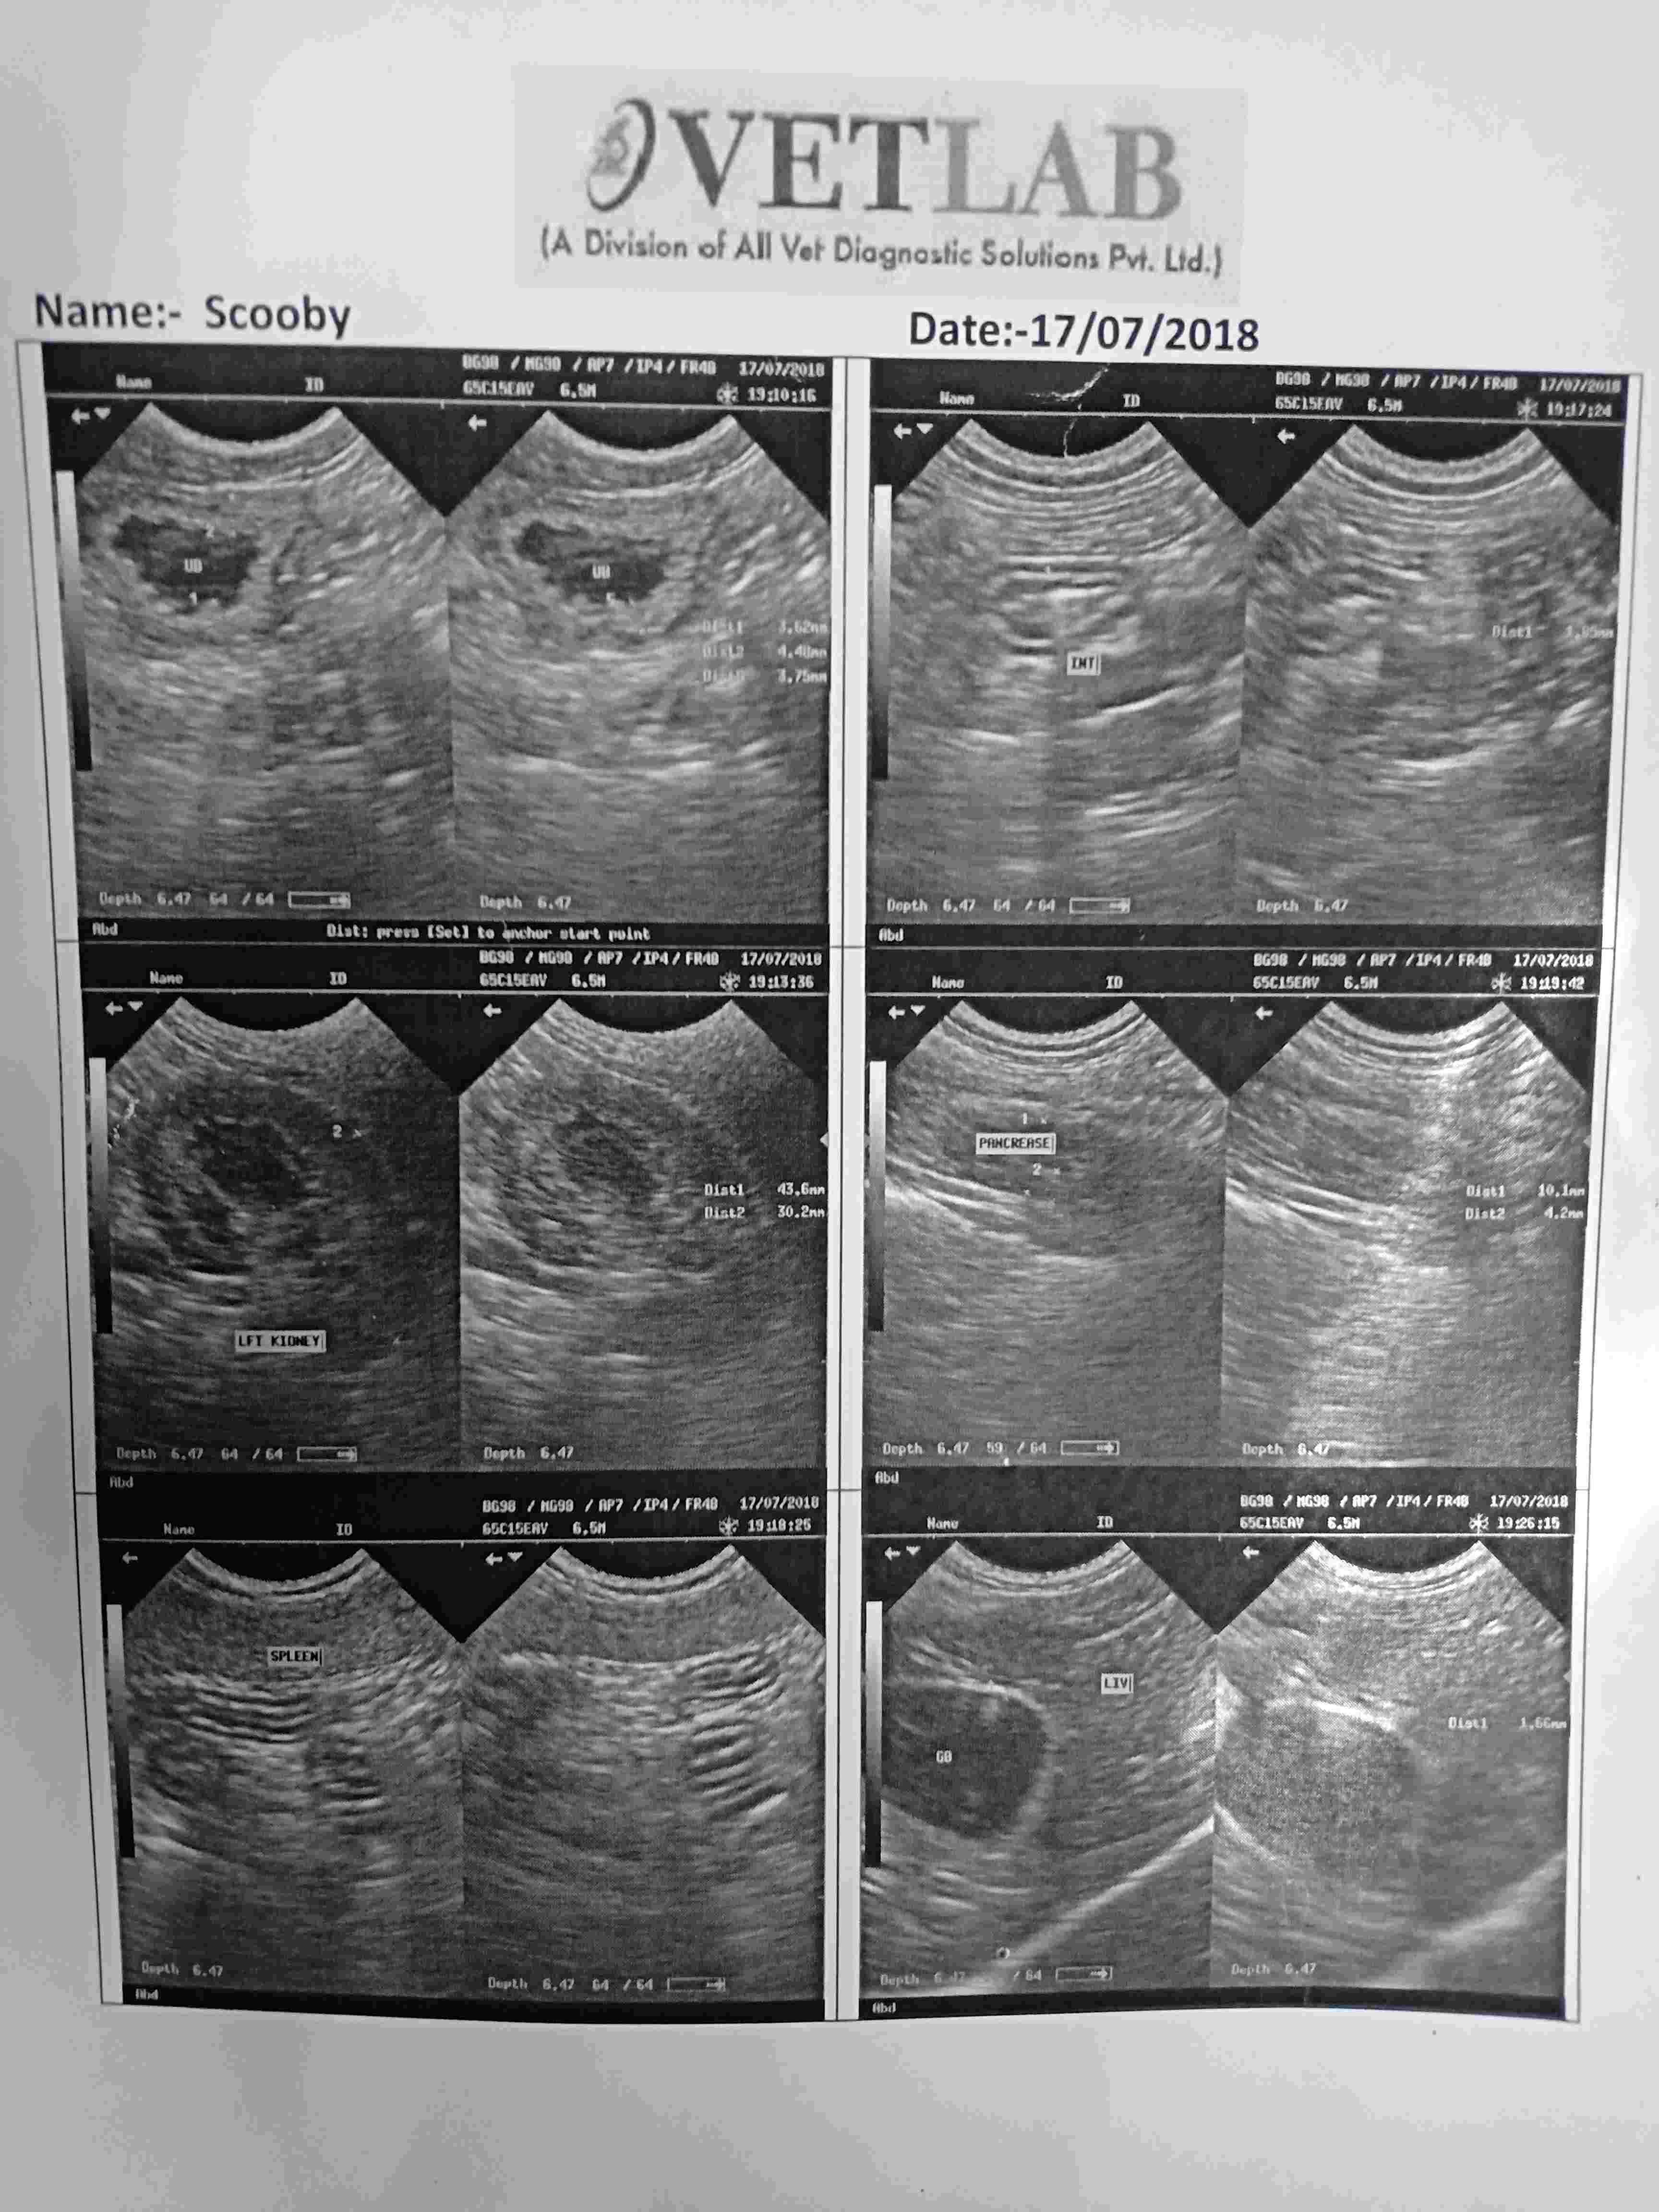

My dog is suffering from IBD what types of food I should give him and what medicine so that the inflammation of his intestine suppress and he can live his normal life as other dog live

Hello and welcome to Petco Pet Education Center, formerly Petcoach. Feeding a high quality, high fiber, low fat, and low allergen diet will be important. Hill's HA or z/d are good places to start, and then you can introduce other foods in slowly, one at a time, to determine what food is causing the allergy. Some dogs do well on Hill's HA, ID or ZD and just remain on that food strictly their whole lives. You can talk to your vet about different immuno-suppressive drugs that can be trialed. Immuno-suppressive drugs have side effects, so using as few drugs as possible is ideal. Also, since Scooby has urinary crystals, you will need to get a food that will help with the crystals as well, especially if you are going to start on immuno-suppressive drugs. Best of luck with Scooby!